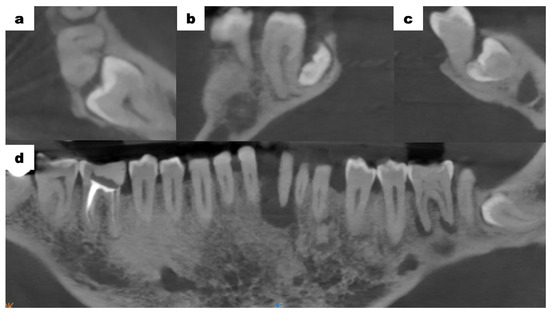

Cone-beam computed tomography (CBCT—cone-beam computed tomography) scans of the mandible, which were provided by the patient, revealed bone resorption around tooth 31. The lateral surfaces of the apices of teeth 41 and 32 were adjacent to the periapical lesion of tooth 31 (Figure 3a). Tooth 46 was treated endodontically for a deficiency of filling material in the apical region of the roots (Figure 3b). Tooth 47 showed a carious lesion. Tooth 36 exhibited extensive periapical changes (Figure 3c). Tooth 38 was partially retained in the horizontal, mesial-angular position with no eruption potential. No inflammatory cysts were found around the crown of the retained tooth. There were no signs of resorption of tooth 37 (Figure 4a). However, the distal root surface of tooth 37 was exposed due to the adjacent position of tooth 38, enabling plaque retention. This might be a potential source of inflammation (Figure 4b). In the event of peri-coronal inflammation, tooth 38 will be eligible for an extraction in the hospital setting. CBCT scans revealed areas of bone thinning in the chin region, potentially due to irradiation treatment when the patient was at the developmental age (Figure 4c).

Figure 3. CBCT examination scans before initiation of treatment; (a) tooth 31—inflammatory change involving the entire root; (b) tooth 46—no trace of filling material in the root canals in the apical region, a suspected periapical lesion; (c) tooth 36—periapical inflammatory changes visible around both roots.